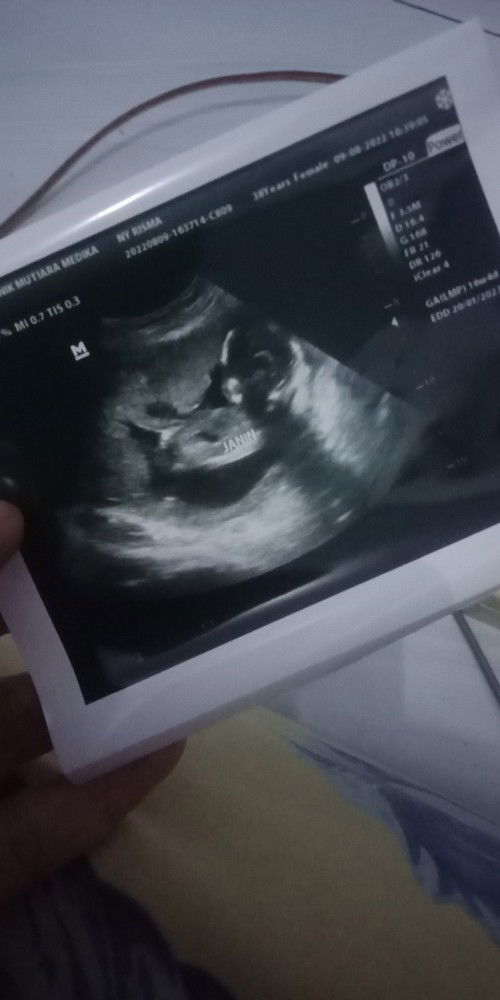

Its a boy yeayyyyyyyy